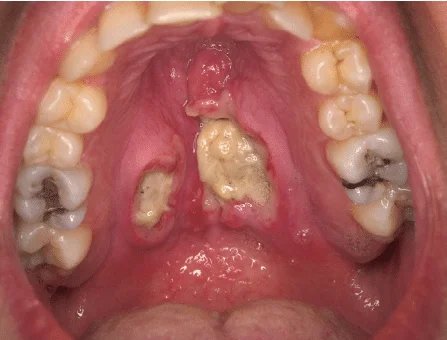

Palate Cancer

Palate cancer develops on the roof of the mouth — either the hard palate (front portion) or the soft palate (towards the throat). It may begin as a small sore, ulcer, or patch that does not heal and can later cause pain, bleeding, or difficulty in swallowing. Because the palate is involved in speaking and eating, even small changes can affect daily life. Faith Hospital, patients receive specialized treatment that focuses on removing the cancer completely while preserving essential functions like speech, swallowing, and appearance. Dr. Zuber Vaja, a skilled Head & Neck Cancer Surgeon, offers precise surgical care along with reconstructive procedures that help patients return to normal life — with confidence and comfort.